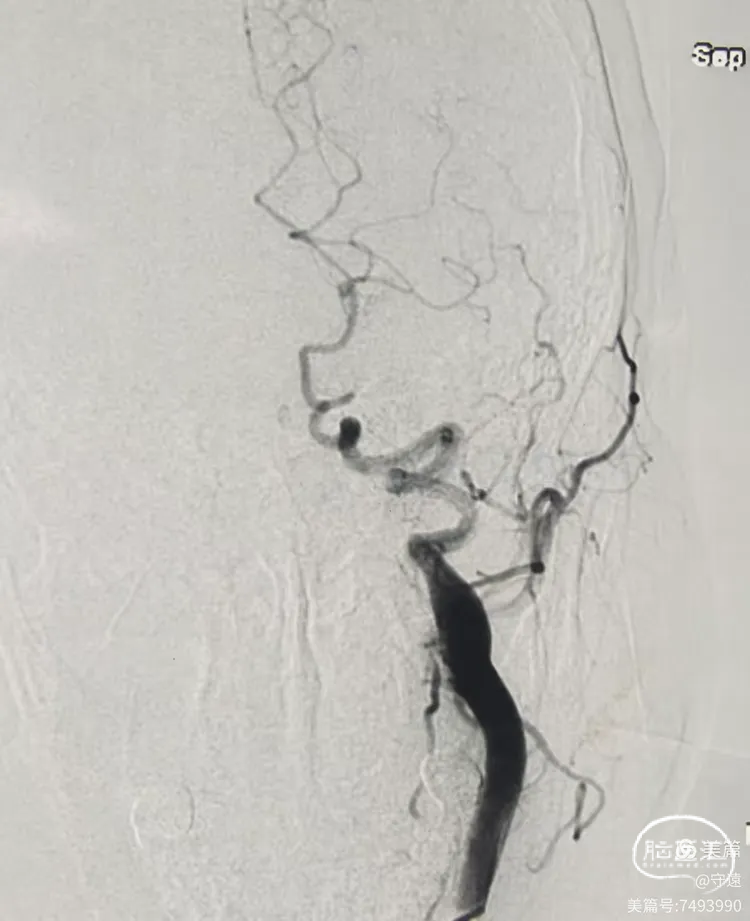

造影显示:左侧大脑中动脉M1以远末显影。

动脉晚期皮层支代偿供血良好,返流至M1段分叉部。

影像评估:M1段闭塞,分叉以远血管床显影良好。

2.造影显示M1闭塞,动脉晚期皮层支返流至M1分叉部。说明闭塞段在M1中段至分叉部。